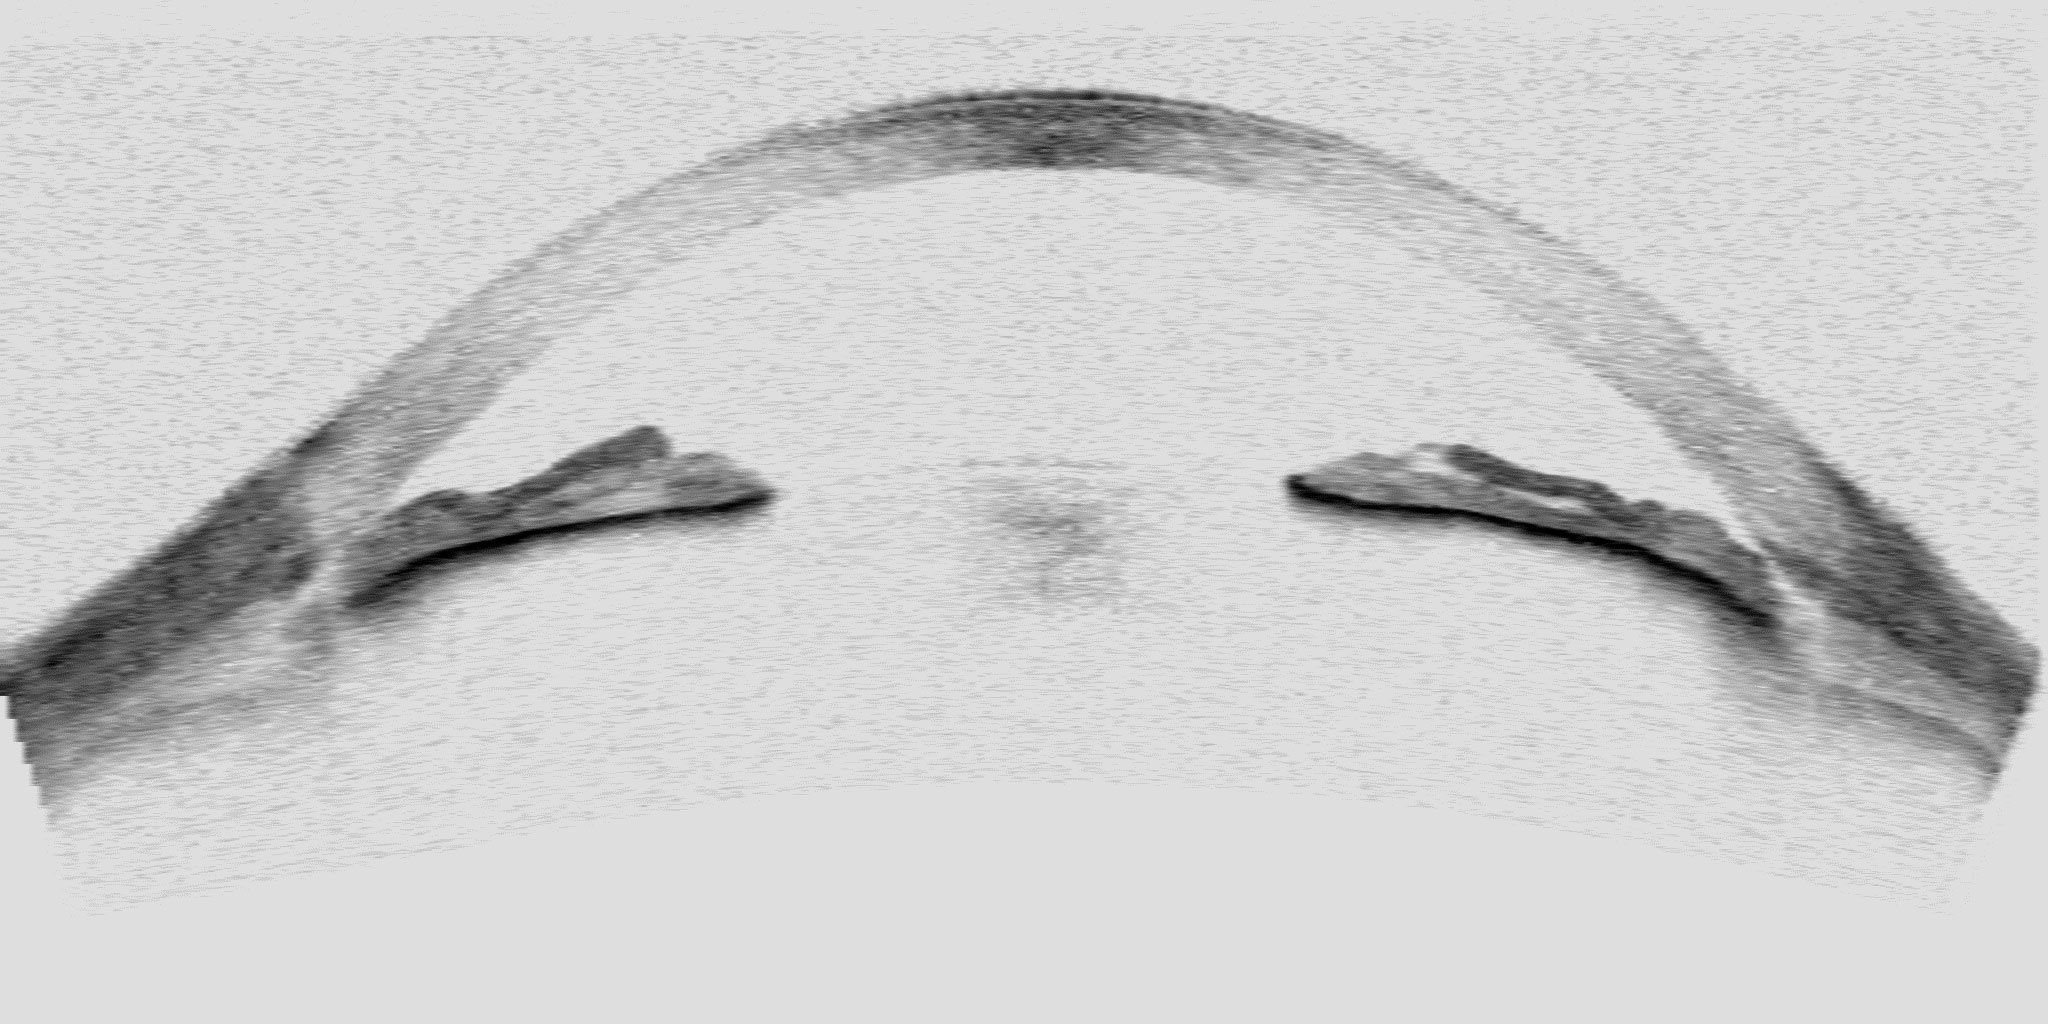

Es tracta del primer mapa tomogràfic de diagnosi del glaucoma que consta de 1.000 imatges tomogràfiques de l’angle irido-cornial preses amb la tècnica OCT (Ocular Coherence Tomography) i ordenades sobre un plànol, de manera que el pacient pot ubicar molt fàcilment l’estat del seu ull en la zona d’angles més tancats (la més greu) i la zona d’angles més oberts (la més lleu).

Tal com explica Pablo Amil, “a l’hora de fer un diagnòstic, l’oftalmòleg compta amb una única imatge tomogràfica de l’ull del pacient que mostra l’estat de l’angle irido-cornial. Si l’angle està molt tancat, el drenatge de fluid intern de l’ull s’obstaculitza i la pressió de l’ull augmenta. Normalment, el diagnòstic del metge sempre és bastant precís, però el pacient no compta amb altres elements comparatius per decidir si s’opera. El meu treball permet als pacients comparar de manera senzilla i objectiva, a través d’un mapa d’imatges, el nivell de gravetat de la seva malaltia i ajudar-los a decidir si s’operen”.